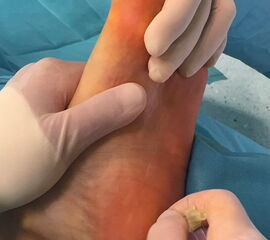

Wachstumsfugen können, wie bereits oben in der generellen Einschätzung des Verfahrens für Kinder und Jugendliche erwähnt, durch direkte Manipulation mit einer Fräse oder indirekt thermisch geschädigt werden. Eine Osteosynthese, die offene Wachstumsfugen kreuzt, ist ausschließlich mit Kirschner-Drähten oder alternativ durch externe Tapezügel möglich. Implantierte Kirschner-Drähte können ohne eine weitere Narkose im Rahmen der Sprechstunde bei verheilter Osteotomie gezogen werden. Die Anwendung von externen Tapezügeln zur Stabilisierung von minimalinvasiven Osteotomien kann bei Kindern ohne Einschränkung durchgeführt werden (siehe Abb. 4 und Abb. 12). Bei sehr jungen Kindern sollten die Tapezügel allerdings nicht zu häufig gewechselt werden, da jeder Verbands- und Tapewechsel Stress für sie bedeutet.

Als günstig erweist sich hier bei den minimalinvasiven fußchirurgischen Techniken die häufig durchgeführte Osteosynthese durch externe Tapezügel (Abb. 4).

Abb. 4 a-c: Beispiel einer minimalinvasiven Kleinzehenkorrektur und Fixation mit Tapezügeln (a-b) oder kombiniert mit Drähten und Tape (c).